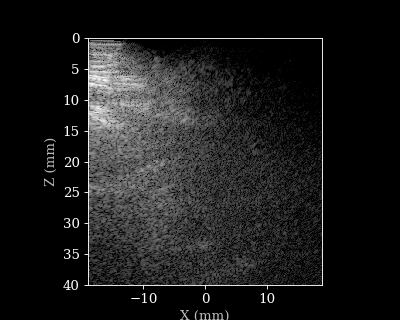

We will load a sequence of acquired RF data frames (carotid scan) and reconstruct a B-mode image from each frame. We will then animate the sequence of images. But first let’s load the data and parameters.

Reconstructing a sequence of B-mode images

B-mode sequence